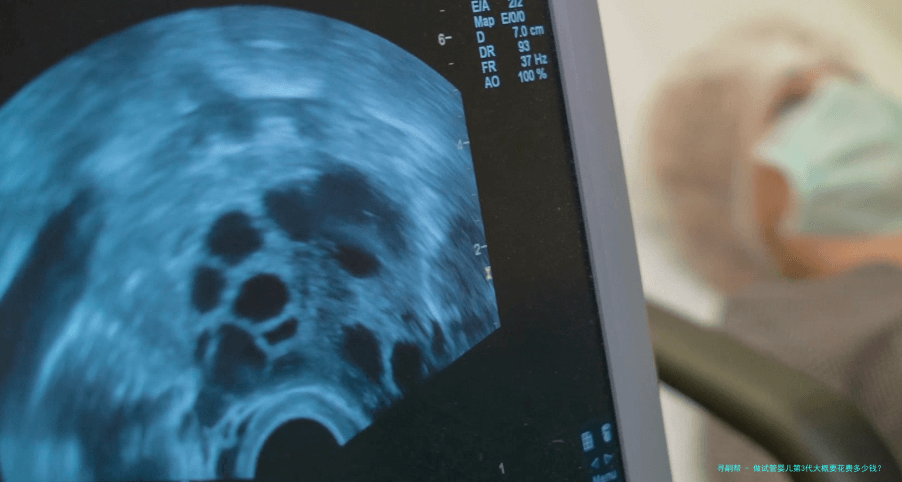

在试管婴儿期间,仍旧要进行一连串的检测项目来确保母体和胚胎状况良好以及顺利发育。这些检查囊括血液检查、超声波检查、基因学检查筛选等,并且屡屡检查都需要支付对应的检测费用。

由于不同人群有不同身体状况和需求,在检查项目上可能会存在差异化抉择及收费标准改动。但全部来讲,所有相关检测项目所需耗费大致在三万块-五万元之间。